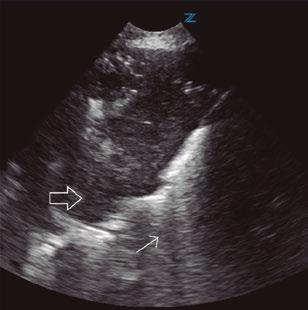

Utilidad clínica de la ecografía pulmonar y cardiaca en urgencias